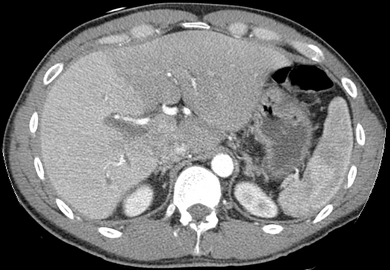

صورة مقطعية محورية تظهر أوردة كبدية شاذة تنتشر على السطح الأمامي تحت المحفظة للكبد.[73]

فحص بالتصوير المقطعي المحوسب يظهر فيه الكبد والوريد البابي.